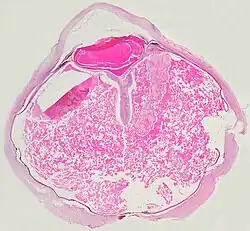

Eine ausgeprägte Netzhautablösung und ein gelbliches Exsudat unter der Netzhaut, das Cholesterinkristalle enthält, sind charakteristisch für den pathologischen Befund.

Unter dem Mikroskop kann die Wand der Netzhautgefäße in manchen Fällen verdickt, in anderen ausgedünnt erscheinen. Hinzu kommt eine unregelmäßige Erweiterung der betroffenen Gefäße.[25] Charakteristisch ist ein Exsudat, das sowohl aus Cholesterinkristallen, mit Cholesterin und Pigmenten beladenen Makrophagen, als auch aus roten Blutkörperchen und Hämosiderin besteht.[26] An der Netzhaut können sich eine durch das Exsudat ausgelöste granulomatöse Reaktion und in manchen Fällen auch eine durch die Verletzung ausgelöste Gliose finden.[27]